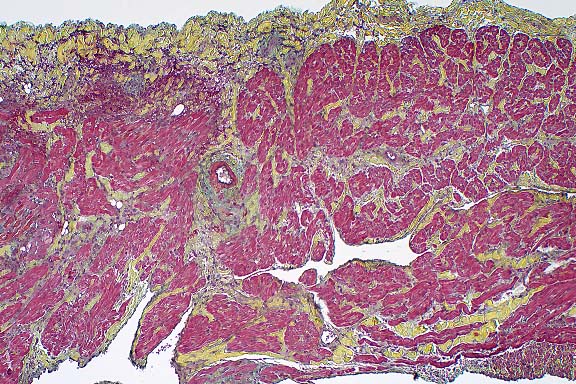

100x

obj

- Case 8-3. Kidney. One or more refractile protozoa

are found within many RBCs of congested interstitial capillaries.

There is fibrillar to amorphous proteinaceous material within

a collecting duct.

40x

- Case 8-3 . Kidney. The glomerulus contains increased

numbers of mesangial cells which compress glomerular capillaries.

Adjacent tubules are filled with eosinophilic material forming

hyaline casts.

Movat

Stain, 4x obj

- Case 8-3. Cardiac muscle. Myocardial muscle is partly

replaced by fibrous connective tissue (fibrosis).

4x

- Case 8-3. Colon. The lamina propria is markedly expanded

by diffuse hemorrhage which distorts and separates the mucosa

from the underlying tunica muscularis.